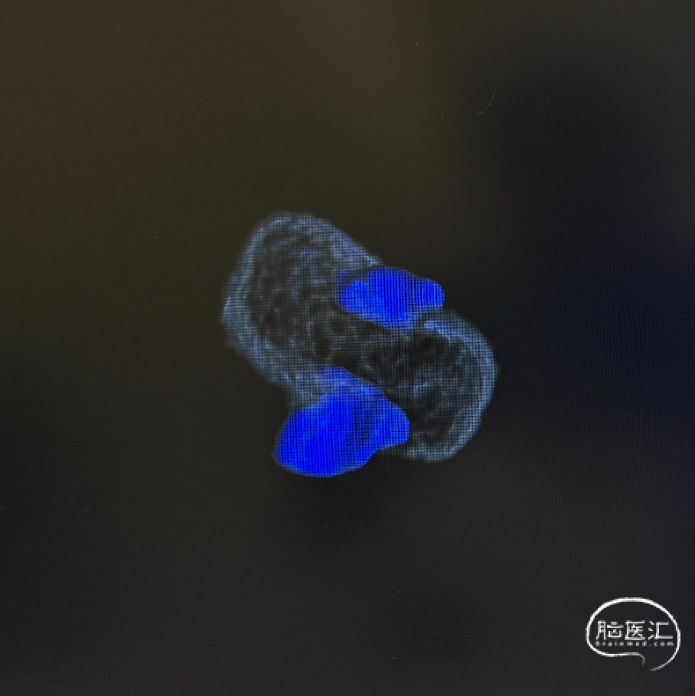

三维旋转图像:左侧大脑中动脉早额支起始部囊性动脉瘤。

术后三维重建及WEB™融合后图像,可见WEB™贴壁良好。

WEB™释放的实时评估:在成角部位,装置展开易受血流冲击影响。需通过多角度造影动态观察WEB™形态,重点确认瘤颈覆盖是否完全、尾端是否充分展开。本例通过反复调整,最终实现装置稳定贴壁,术后利用西门子自带多容积三维重建,分析扰流装置的位置,证实了技术操作的可靠性。